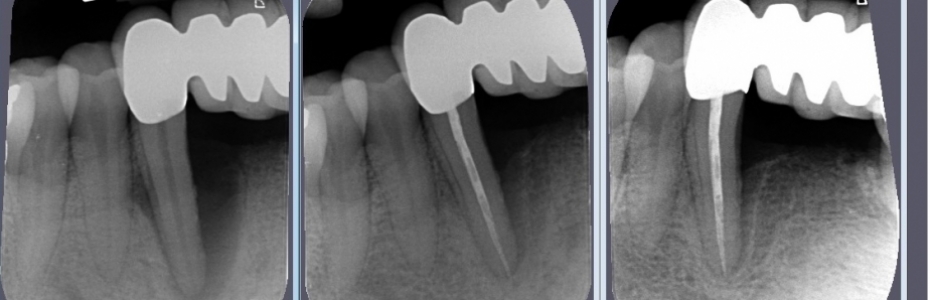

Hat sich der Zahnhalteapparat aufgrund einer Parodontitis abgebaut, kann dieser je nach Ausprägung des Abbaus wieder aufgebaut werden. Idealerweise sollte der neue, wieder aufgebaute Zahnhalteapparat sowohl in der Form als auch in der Funktion die gleichen Eigenschaften besitzen, wie der Ursprüngliche.

Für die regenerative Behandlung ausgeprägter, parodontaler Defekte bieten sich unterschiedliche Methoden an. Es gibt nur wenige Gewebe, die nach einem Defekt in der Lage sind, sich ohne Narbenbildung oder Funktionseinbußen zu regenerieren.

Diese Proteine ermöglichen Ihrem Körper den natürlichen Zahnhalteapparat wieder herzustellen, indem sie die Prozesse, die während der Zahnentwicklung stattfinden, nachahmen. Die Wiederherstellung des Zahnhalteapparats (Wurzelzement, Faserbündel und Knochen) beginnt unmittelbar nach der Behandlung mit Schmelzmatrixproteinen und setzt sich über einen längeren Zeitraum fort.

Durch die Anwendung von regenerativen Methoden mit Schmelz-Matrix-Proteinen soll vermieden werden, dass es zur Bildung von Narben- und Bindegewebe kommt.